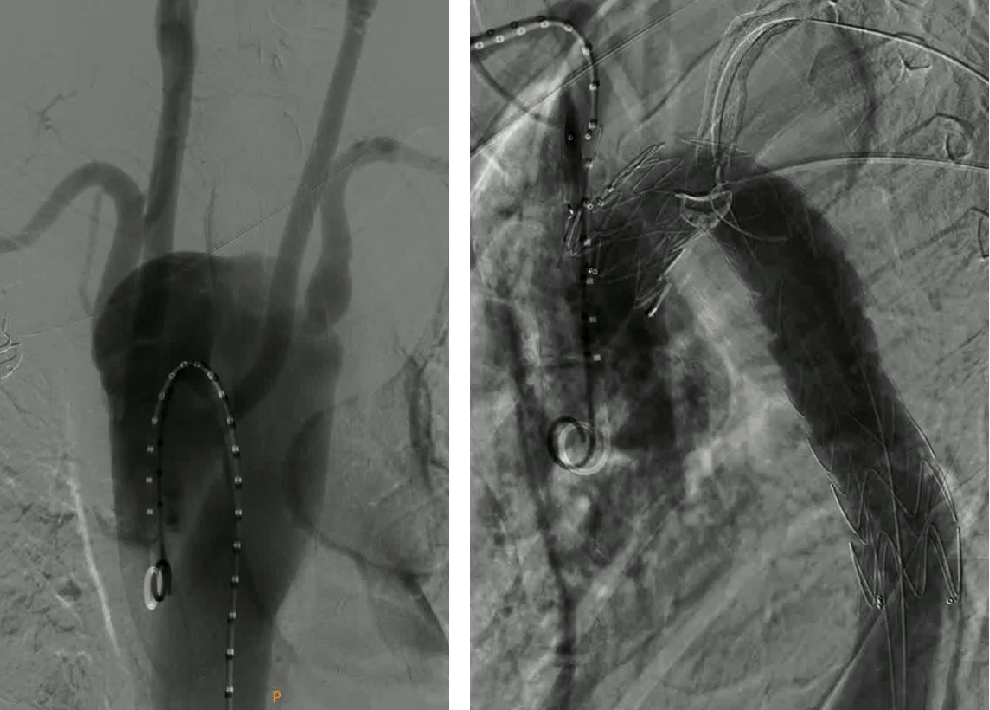

★Case 2 穿透性溃疡,右位弓

治疗难点:右位弓,锚定区不足、四分支走行变异,LSA重度狭窄

治疗目的:重塑主动脉形态,保障弓上四支变异分支血管正常供血

手术策略:TEVAR+烟囱(右锁骨下动脉)+潜望镜(左锁骨下动脉)

结果:四支血管血运恢复,术后造影血流通畅

释放主体支架

建立左锁骨下轨道

建立潜望镜